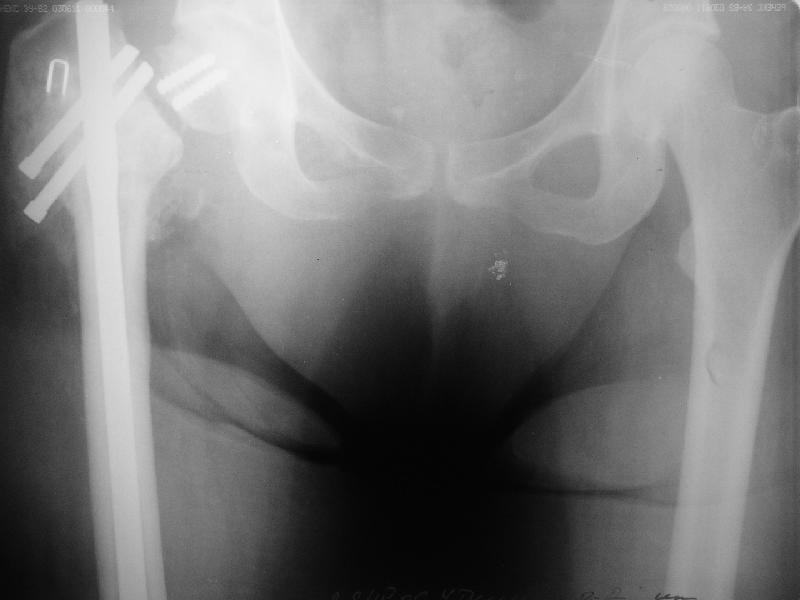

Уважаемые коллеги, хотелось бы услышать ваше мнение по следующему случаю: Относительно молодая женщина(39 лет), поступила в клинику в марте 2005 года, через 3 месяца после травмы с Неправильно срастающимся поперечным межвертельным переломом правого бедра. Был выполнен закрытый интрамедуллярный остеосинтез правого бедра канальным реконструкционным стержнем ChM. Ожидали бОльших проблем на операции, результату обрадовались. Как оказалось, зря. Сращение наступило через 3,5 месяца после операции. В ноябре 2005 года произошел перелом шейки бедра и винтов в ней. В апреле 2006 импланты были удалены. В приложении фото и рентгенограммы больной. Сопутствует ожирение 4 ст. (при росте 168 см., вес больной 140кг.), сахарный диабет II тип. Имеется медиальная неустойчивость коленного и голеностопного суставов, при нагрузке колено вальгируется на 15-20 градусов. Вопросы: 1.Целесообразность эндопротезирования (в настоящий момент передвигается на ходунках)? 2.Если ответ на первый вопрос-да, то каким протезом? 3. С какими проблемами можем столкнуться во время и после операции? Заранее благодарен за ответы. Салават Салаватов, Екатеринбург